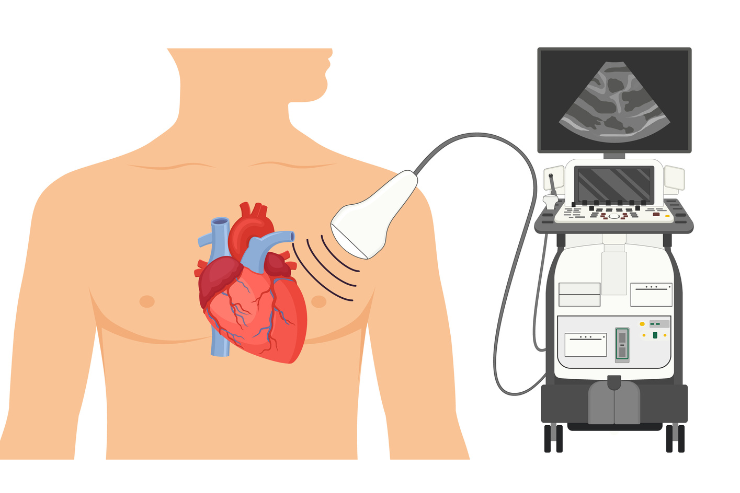

Echocardiography

Echocardiography (ECHO) is a non-invasive imaging technique that uses ultrasound waves to create detailed images of the heart. It helps assess heart function, structure, and blood flow, allowing for the diagnosis of conditions such as valve disorders, heart failure, and congenital heart defects. ECHO is a vital tool for guiding treatment decisions and monitoring heart health effectively.